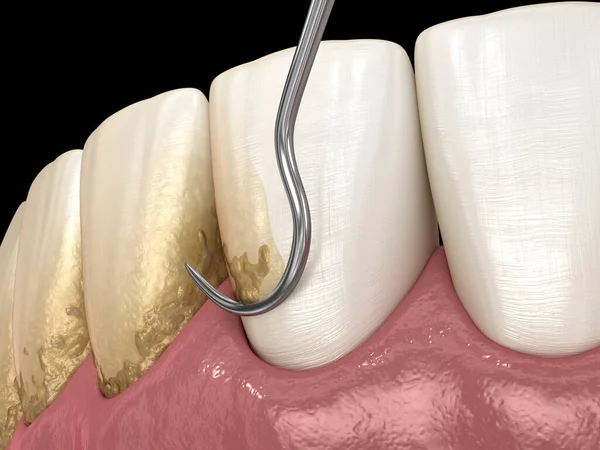

Laserterapia

O uso do laser de baixa potência auxilia na descontaminação das bolsas periodontais, reduz a sensibilidade e acelera a cicatrização dos tecidos em até 3x.